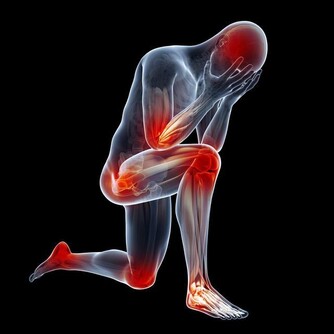

用患者的話說是:“感覺被世界遺棄”、“我寧可斷只胳膊或斷條腿”、“每次呼吸都像被刀子扎一樣”……

另外,除了身體上每天要遭受“生不如死”的痛苦外,半數的空鼻症患者還伴有精神抑鬱症狀。